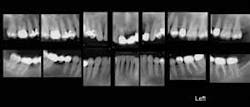

Full-mouth periapical radiographic series (Fig. 1): When many teeth are in the mouth, most dentists prefer making periapical radiographs of all of the teeth. A typical full-mouth series includes the following separate images: molars (4), premolars (4), canines (4), anterior teeth (2), for a total of 14 separate images. These 14 images are usually augmented with four bitewing radiographs. If many teeth are missing, only a few periapical radiographs are usually indicated. If only a few teeth are remaining in the mouth, a panoramic radiograph may be adequate. The ability of either analog (D-speed film) or digital radiographs to show initial dental caries has been studied and compared. Neither type of radiograph shows initial caries well. Additionally, panoramic radiographs do not show initial caries. Some dentists have eliminated the 14-to-18 image, full-mouth series and use only panoramic radiographs. Patient education using only periapical radiographs is difficult, since many teeth are duplicated in the various views, and this is confusing to patients.